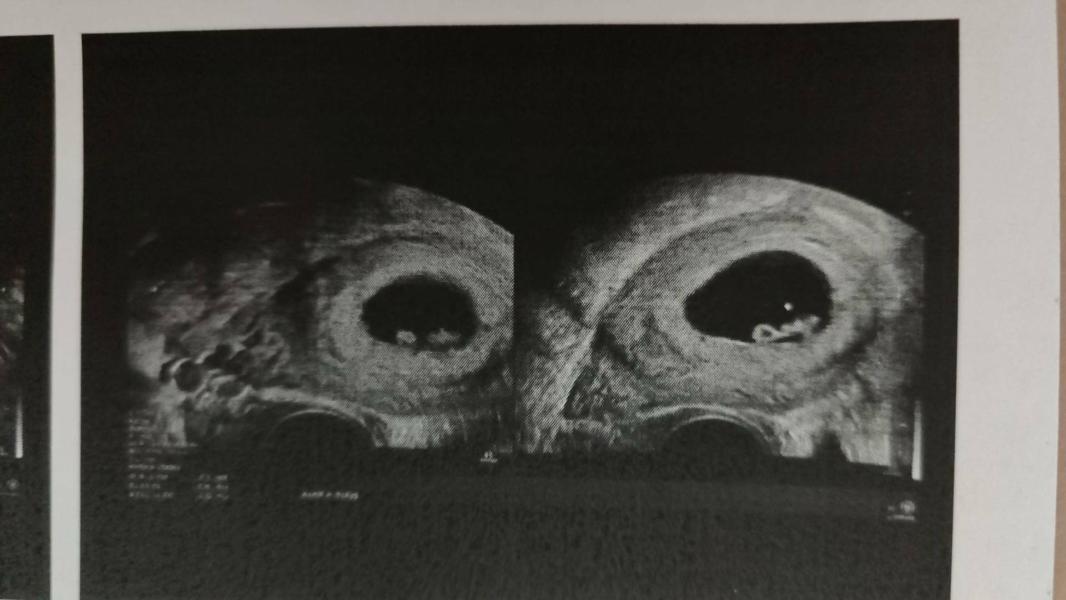

Ну что, привет, малышок, ты еще такой крошка🥰 всё по срокам, чсс 170, хоромы большие, я спокойна🤗😍